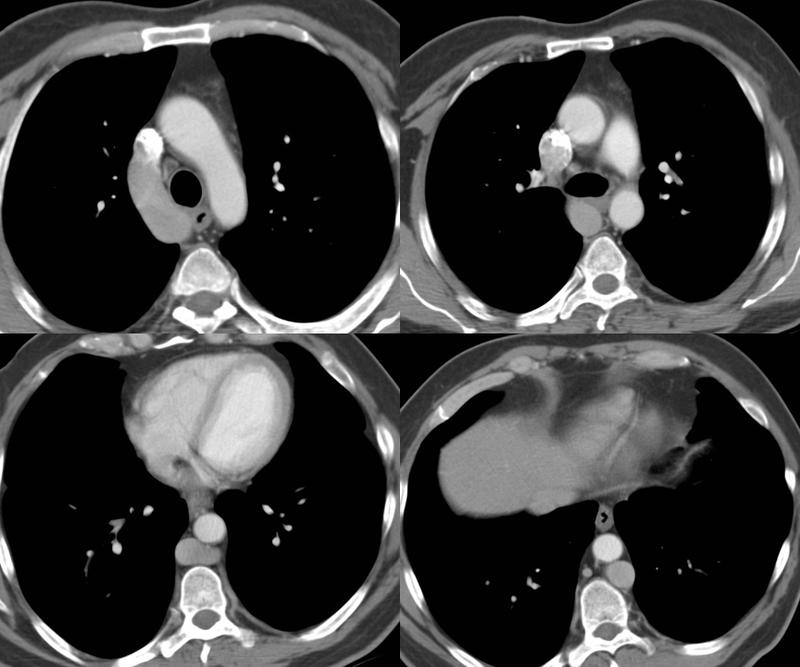

Gallery Congenital Azygous continuation

Azygous continuation